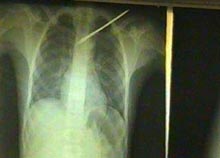

RADIOGRAFÍA DEL PEQUEÑO DONDE SE PUEDE APRECIAR EL PELIGRO QUE REPRESENTABA EL AFILADO DARDO PARA LA VIDA DE OUSMANE.

El galeno apreció las circunstancias: tenía casi 72 horas de evolución sin repercusión hemodinámica ni respiratoria, y decide intervenir quirúrgicamente en las cercanías del corazón. De inmediato el niño Ousmane Mahamadou fue sometido a exámenes radiológicos y otros complementarios.